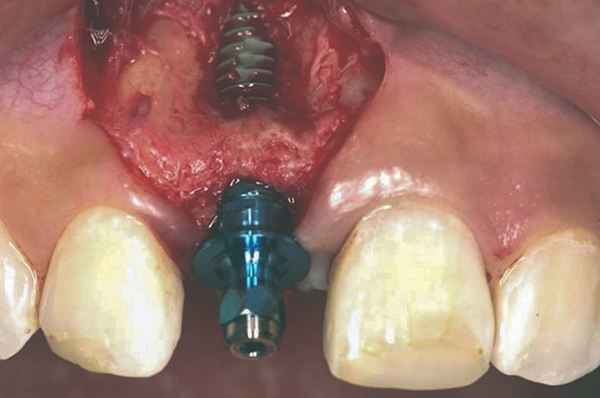

Fig 4. Implant inserted into the ridge, buccal view. There was a large labial concavity. The implant is seen on the buccal and terminates within the alveolar bone.

Figure 4